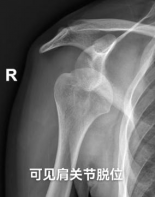

患者李先生,38岁,5年前因外伤导致右肩关节脱位,当时予手法复位后关节逐渐恢复运动,2年前因轻微外伤后再次出现脱位,此后开始出现多次脱位,两年期间,行6次肩关节手法复位术,且出现脱位的间隔时间逐渐缩短,睡眠过程中、打哈欠时均伴随剧烈的疼痛,严重影响患者生活质量。

此次李先生想要彻底摆脱病痛折磨,来pilipili 骨科门诊找到黄林主任,黄主任查体后诊断:右肩关节复发性脱位伴前向不稳,右肩Hill-Sachs损伤。通过CT检查发现患者的肩胛盂前盂唇缺损过大,肱骨头后缘存在较大的缺损(Hill-Sachs损伤),肩胛盂前侧骨缺损大于20%,单纯的肩关节镜下软组织修复术无法取得满意的疗效。